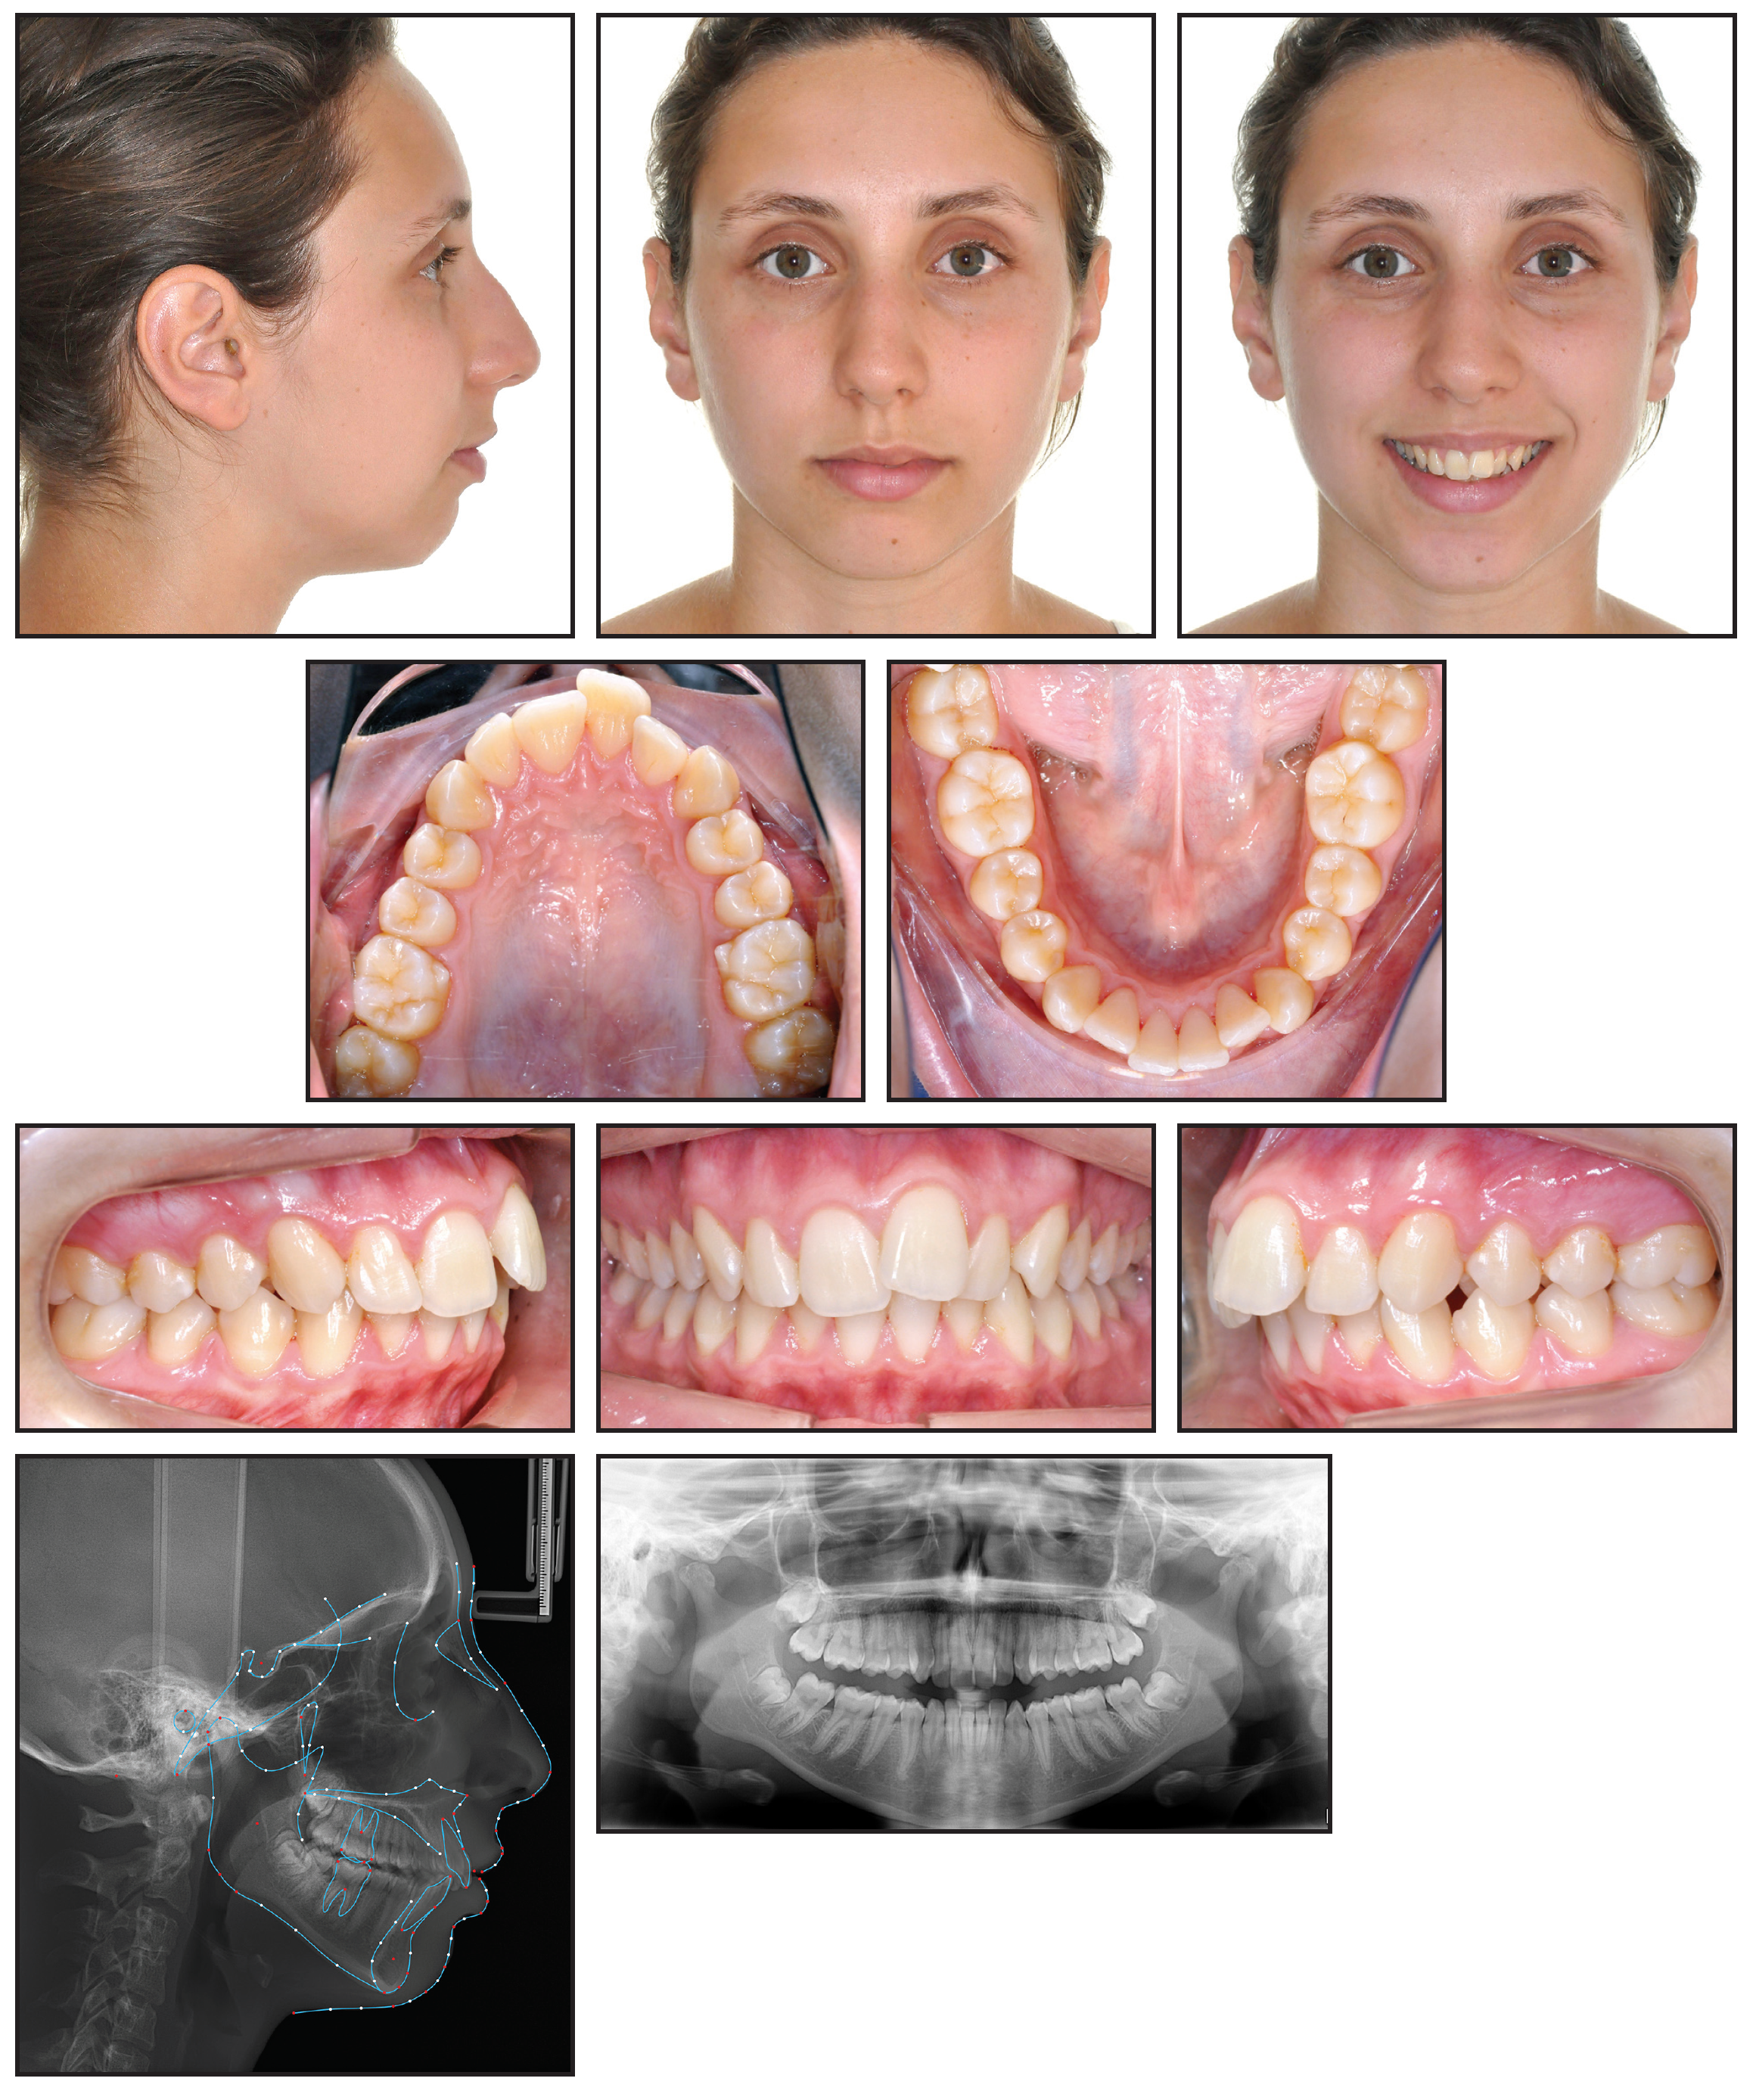

March 2019 Issue Highlights THE CUTTING EDGE Face Scanning and Digital Smile Design with an Intraoral Scanner Dr. Giovanni Battista demonstrates how a digital setup and smile plan can be produced by importing intraoral scans into computer-aided design software, without the need for more expensive and invasive cone-beam computed tomography or facial scans.